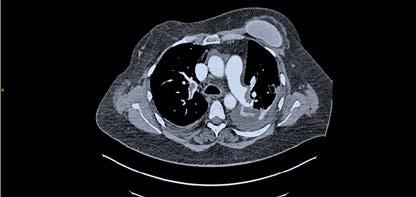

Se realizó una tomografía computarizada (TC) con contraste de forma emergente, que mostró una disección aórtica iatrogénica tipo A focal de origen en la zona 0 del cayado con extensión al tronco braquiocefálico derecho (1) sin afectar al resto de troncos supra-aórticos, cayado o aorta descendente (Figuras 1 y 2); además del hematoma

IATROGÉNICA. ¿QUÉ PUEDE SALIR MAL?

Figuras 1 y 2: Prótesis aórtica migrada y disección aórtica focal tipo A, de origen en la curvatura menor del arco aórtico (zona 0) hasta la bifurcación de la arteria braquiocefálica derecha; sin afectación de del resto de troncos supra-aórticos, del resto del cayado aórtico o de la aorta descendente.